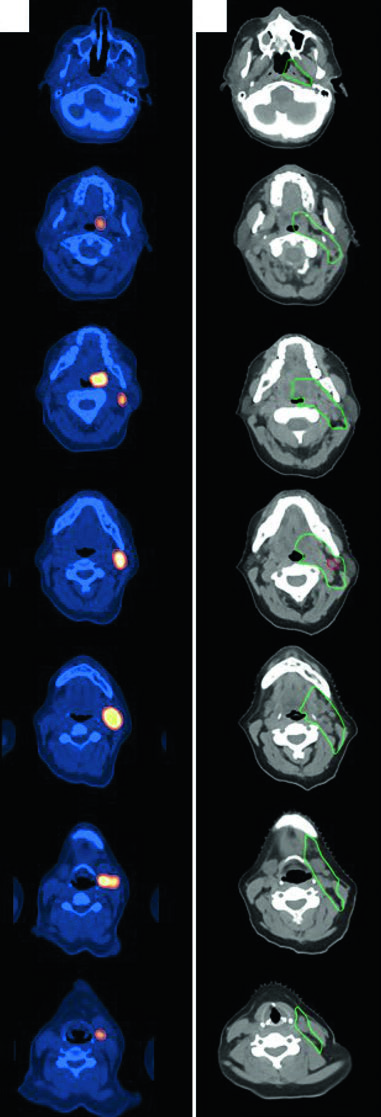

ISRT delineation for nodular lymphocyte-predominant Hodgkin lymphoma stage IIA with right supraclavicular, subpectoral, and axillary disease treated with definitive RT

Figure 31.3 — NLPHL stage IIA: GTV (red), ISRT CTV (green), and PTV (blue) with definitive RT. Source: Target Volume Delineation and Field Setup, 2nd Edition

Nodular Lymphocyte-Predominant HL (NLPHL)

A 61-year-old man with stage IIA NLPHL involving right supraclavicular, subpectoral, and axillary nodes was treated with definitive RT alone. Simulated with arms up using a wingboard. The diagnostic PET was fused to the simulation CT. As RT was the sole modality (no chemotherapy), more generous CTV margins were necessary to cover potential subclinical disease.

Axial slices of PET-CT and simulation CT showing ISRT delineation for diffuse large B-cell lymphoma of the left tonsil and neck level 2

Figure 31.4 — DLBCL of tonsil and neck: pre-chemo GTV (red), post-chemo GTV (red), and ISRT CTV (green) covering the involved nodal level. Source: Target Volume Delineation and Field Setup, 2nd Edition

A 47-year-old woman with stage IIA DLBCL of the left tonsil and left neck (level 2, 5.6 cm) received 3 cycles of R-CHOP followed by consolidation RT. Simulated with neck in extension, immobilized with 5-point aquaplast mask. The ISRT CTV covers the entire left tonsil and left neck nodal level, including 1–2 cm superior and inferior to the pre-chemotherapy disease extent. Head and neck lymphoma cases require meticulous attention to registration between diagnostic PET and simulation CT.